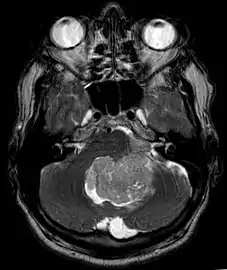

An ependymoma is a tumor that arises from the ependyma, a tissue of the central nervous system. Usually, in pediatric cases the location is intracranial, while in adults it is spinal. The common location of intracranial ependymomas is the fourth ventricle. Rarely, ependymomas can occur in the pelvic cavity.

Ependymomas make up about 5% of adult intracranial gliomas and up to 10% of childhood tumors of the central nervous system (CNS). Their occurrence seems to peak at age 5 years and then again at age 35. They develop from cells that line both the hollow cavities of the brain and the canal containing the spinal cord, but they usually arise from the floor of the fourth ventricle, situated in the lower back portion of the brain, where they may produce headache, nausea and vomiting by obstructing the flow of cerebrospinal fluid. This obstruction may also cause hydrocephalus. They may also arise in the spinal cord, conus medullaris and supratentorial locations.[4] Other symptoms can include (but are not limited to): loss of appetite, difficulty sleeping, temporary inability to distinguish colors, uncontrollable twitching, seeing vertical or horizontal lines when in bright light, and temporary memory loss. It should be remembered that these symptoms also are prevalent in many other illnesses not associated with ependymoma.